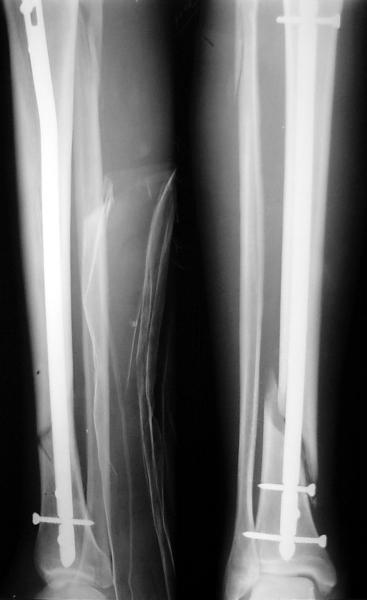

По крайней мере ходящих без дополнительной опоры через 1 месяц после операции с небольшой - при изолированной травме немало. Нестабильные по оси, кстати, не только оскольчатые, но и спиральные.

Как мне показать пример? Фото стоящего на одной оперированной конечности пациента? O! Пример, подвигнувший нас на некоторое изменение технологий. Пациент этот ходил с полной нагрузкой вопреки рекомендациям. В качестве подтверждения - сломанный проксимальный статический винт к 1 мес., а к 2 мес. - все остальные. Сейчас мы перешли на более fool-proof остесинтез.

На мой взгляд, на снимках, приведённых Вами - неправильно сростающийся перелом дистальной трети большеберцовой кости, состояние после остеосинтеза интрамедуллярным гвоздём.

Как Вы пишите снимок под номером 1 - менсяц после операции, под номером 2- два месяца после операции.

Вы не послали послеоперационный снимок, поэтому трудно судить о состоянии редукции после операции.

Установка с медиальной стороны гвоздя в области дистального фрагмента дополнительного шурупа помогло бы Вам репонировать и удержать перелом в анатомическом положении, предотвратило варусную деформацию и смещение по ширине.

На мой взгляд внутрикостная фиксация переломов дистальной и проксимальной трети большеберцовой кости, за исключением поперечных, не очень хорошее решение вопроса, аппарат Илизарова или Тэйлора, позволяющие призвести закрытую анатомическую редукцию и отличное удержание отломков в период сращения.

Пример, приведённый Вами в нашей дискуссии по времени нагрузки после остеосинтеза не совсем удачный... Ваш больной имеет счастье, что первым согнулся проксимальный замыкающий винт, а не дистальный и гвоздь не пенетрировал голеностопный сустав.

I think that the X-Rays show S/P IMN of Spiral # of the Distal Tibia consoles in misalignment.

You wrote that a picture number 1 - f month after the surgery, and number 2-two months after the surgery.

You have not sent a postoperative X-Rays; so it's impossible to discuss about the condition of a reduction after operation.

Let to express concerning technique of operation my opinion... Insertion of a screw to medial side of a nail in distal fragment would help you to reduction and to keep this fracture in anatomic position has prevented varus deformity and displacement on width. By the way, if it is possible send a postoperative picture.

In my opinion IMN of fracture distal and proximal thirds of the tibia bones, except for transverse, not so good decision of treatment. Ilizarov or Taylor external fixators allow to the closed anatomic reduction and excellent fixation such fractures during the consolidation period.

Your patient is lucky enough, that by the first was bent proximal locking screw, instead of distal and a nail does not penetrate to the ankle joint.

Это наглядная демонстрация возможности ранней полной нагрузки при нестабильном по оси повреждении, причем не в самых благоприятных механических условиях - при плохом сопоставлении, со слабым фиксатором.

Сверху - один статический винт, а снизу - три. Что раньше сломается? Конечно, он потом и нижние сломал, и Вы правы, если бы верхний динамичесий винт уже уперся бы в нижний край отверстия, будь гвоздь подлинее, перфорировал бы сустав как пить дать.

Как я уже говорил, мы сделали выводы из этого и других подобных случаев. Очевидно, решений проблемы два - либо уменьшить нагрузку, либо увеличить прочность фиксатора. Первое решение работает не со всеми больными, так что пошли по второму пути - мы больше не используем гвозди с запирающими винтами диаметром 4 мм.